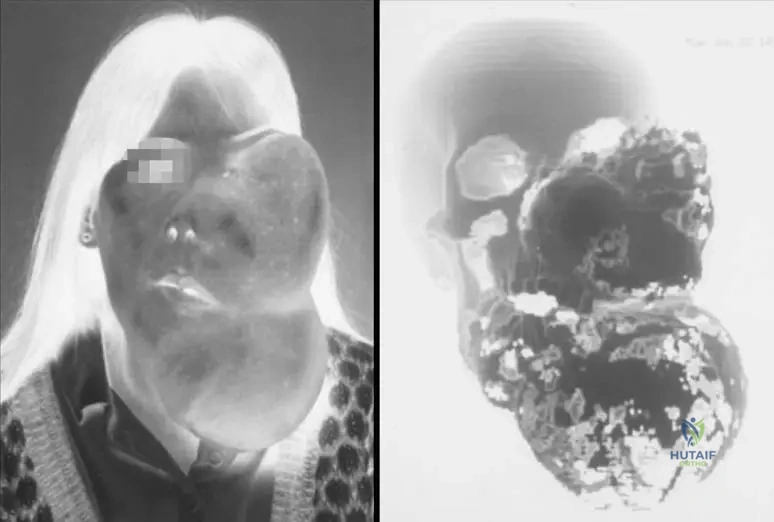

A 20-year-old patient presents with significant asymmetry and swelling of the left side of their face and jaw, causing cosmetic and functional concerns. A 3D CT scan reveals extensive involvement of the facial bones.

View Answer & Explanation

Correct Answer: A

Rationale: The text explicitly states, "Skull and facial lesions can cause significant deformity, exophthalmos, etc." The image (Fig. 11.25 a, b) also visually demonstrates "Massive deformity secondary to fi brous dysplasia of the left face and jaw." Main Distractor Rationale: Option B is incorrect. Acute respiratory distress syndrome is not a direct consequence of fibrous dysplasia affecting the facial bones.

A 20-year-old patient with extensive fibrous dysplasia of the left face and jaw presents with significant facial asymmetry and difficulty closing their eyelid. Which specific complication is directly mentioned as a potential consequence of skull and facial lesions in fibrous dysplasia?

Correct Answer: C

Rationale: The text states that "Skull and facial lesions can cause significant deformity, exophthalmos, etc." Exophthalmos (protrusion of the eyeball) is a direct complication mentioned. While other complications might occur, exophthalmos is specifically listed.